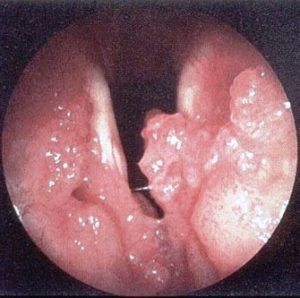

Фото операції з видалення папилломатоза в горлі

Видалення папілом роблять звичайним скальпелем, випалюють лазером, рідким азотом і електричним струмом. Метод видалення залежить від віку пацієнта, локалізації папілом і можливостей лікарні.